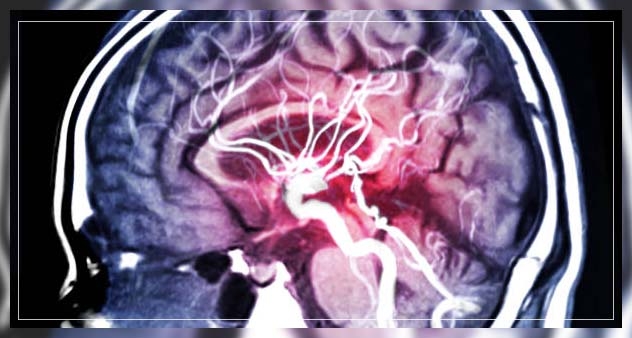

dementia